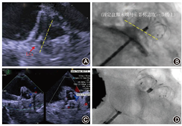

连续性纳入上海市第十人民医院自2014年4月至2019年3月31日拟行LAAC的房颤患者。共计563例经过筛选尝试行左心耳封堵术(图8),550例植入左心耳封堵器,13例没有植入封堵器,未植入的原因包括1例双侧股静脉变异致鞘管不能通过放弃手术;2例左心耳造影前发现"心包填塞"放弃继续LAAC;4例尝试植入PLO失败且拒绝择期行补救性DLO,均为开口大的左心耳,2例合并可用深度较浅(图9 A~D);5例完成左心耳造影后放弃尝试植入PLO,其中3例为多分叶且较浅(图9 E~G),1例为极小左心耳(图9H),1例为反鸡翅且可用深度较浅(图9I);1例左心耳开口较大且口部梳状肌放弃植入封堵器。该例尝试植入36 mm×40 mm LAmbre,释放封堵器后脱落至左心房内,成功经导管回收(图9 J~K),放弃继续植入封堵器。

3例在完成LAA造影后,放弃尝试植入PLO,择期行LAmbre封堵器补救,2例成功(1例使用最大型号LAmbre封堵器36 mm×40 mm ,1例使用特殊型号LAmbre封堵器18 mm×32 mm,图10),1例使用2个LAmbre封堵器但仍封堵失败(图11)。

6例尝试植入PLO不成功,行补救性DLO植入,均成功封堵,使用LAmbre封堵器5例和Leftear封堵器1例。其中3例使用较大型号封堵器(图12),31 mm×35 mm 1枚(Leftear封堵器)和36 mm×40 mm 2枚,1例使用最小型号LAmbre封堵器(图13)16 mm×22 mm、2例使用特殊型号LAmbre封堵器24 mm×36 mm及22 mm×34 mm。

19例左心耳形态不合适PLO植入的病例中,有10例左心耳不适合使用DLO植入失败或未尝试也拒绝择期植入DLO,有9例使用DLO补救。从左心耳形态分析,1例为开口极小且分叶(图13) A,开口大(>32 mm)5例(图10A、图11、图12A、图12B、图12C)、分叶且较浅3例(图10B、图13B、图13C)。从补救使用的DLO分析,使用大尺寸封堵盘(封堵盘>32 mm)的封堵器达到88.9% (8/9),1例使用最小型(固定盘16 mm,封堵盘22 mm),提示DLO比PLO覆盖更多的左心耳开口尺寸。使用"小伞大盘"特殊型号封堵器3例,封堵盘比固定盘大12~14 mm,均植入于多分叶的病例(图10B、图13B、C),固定盘固定于某一分叶。提示DLO中"小伞大盘"的特殊类型,更能适用于多分叶的左心耳。